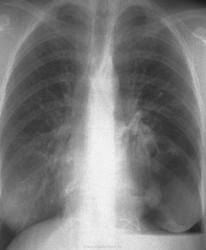

Рентгенодиагностика. Играет ведущую роль. Рентгенологические признаки кистозной гипоплазии можно разделить на три группы:

1. свидетельствующие о существовании множественных полостных образований в легких;

2. отражающие уменьшение органа или его части в объеме;

3. указывающие на наличие хронического воспалительного процесса в нижерасположенных участках бронхиального дерева.

К первой группе признаков относится наличие в области аномалии характерного ячеистого легочного рисунка, являющегося отражением множественных тонкостенных воздушных полостей. Наиболее часто ячеистый рисунок при кистозной гипоплазии наблюдается в области верхней доли правого легкого или же занимает все левое легкое.

Об уменьшении объема недоразвитой части легкого можно судить по смещению междолевой границы (в случае долевой гипоплазии) для средостения в сторону поражения, что более характерно для гипоплазии легкого, хотя может наблюдаться и при поражении доли.